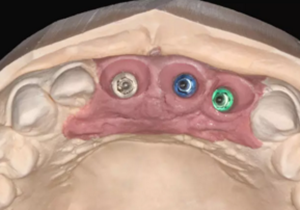

(1)術(shù)前準(zhǔn)備。拍攝臨床照片、拍攝輕開口位CBCT(NewTom)、取聚醚印模灌制超硬石膏模型。 構(gòu)建數(shù)字化模型并設(shè)計修復(fù)體:將超硬石膏模型在口外掃描(Identica? Hybrid),獲取軟硬組織表面形態(tài),構(gòu)建數(shù)字化模型,確認(rèn)咬合情況。根據(jù) 天然牙殘根頸部形態(tài)設(shè)計修復(fù)體頸部形態(tài),使修復(fù)體頸緣輪廓與原有天然牙 一致;按正常牙弓弧度與覆 、覆蓋關(guān)系,結(jié)合紅白美學(xué)等原則確定修復(fù)體 的三維形態(tài)。最后,導(dǎo)入患者面部照片,確認(rèn)模擬修復(fù)效果。 設(shè)計種植體位置并制作多級導(dǎo)板:利用Segma設(shè)計軟件,將CBCT數(shù)據(jù) 和模型掃描數(shù)據(jù)進(jìn)行配準(zhǔn),調(diào)入模擬修復(fù)效果數(shù)據(jù),以修復(fù)為導(dǎo)向設(shè)計種植 方案,設(shè)計種植體螺絲孔開口從修復(fù)體舌窩處穿出,最終實現(xiàn)螺絲固位的一 體化基臺冠修復(fù)。根據(jù)種植體信息設(shè)計多級導(dǎo)板,參考修復(fù)體形態(tài)設(shè)計導(dǎo)板 植入?yún)^(qū)頸緣外形,打印生成種植導(dǎo)板(Segma),并安裝金屬引導(dǎo)環(huán)。 設(shè)計并制作臨時修復(fù)體:如前所述,按照美學(xué)效果和咬合關(guān)系設(shè)計臨 時冠外形,頸部形態(tài)與模型齦緣輪廓一致,保證臨時修復(fù)體在術(shù)后可以封閉 拔牙窩。3顆臨時冠為連冠,齦外展隙適當(dāng)加大,為術(shù)后軟組織生長提供一 定的空間。在臨時冠近兩側(cè)鄰牙的切角處預(yù)留翼板,保證臨時冠戴入時可以 找到準(zhǔn)確的位置。以銑削的方式加工臨時冠(Segma),待種植體植入后 將其在口內(nèi)粘接于臨時基臺上。

(2)即刻種植、即刻臨時修復(fù)。術(shù)中不翻瓣微創(chuàng)拔除牙根,牙槽 窩骨壁完整。在多級導(dǎo)板輔助下完成種植窩洞制備,植入Bego柱形種植 體,型號分別為:上頜右側(cè)中切牙位點(diǎn)4.1mm×15mm、上頜左側(cè)中切牙 位點(diǎn)?3.75mm×15mm、上頜左側(cè)側(cè)切牙位點(diǎn)3.25mm×15mm,扭矩均為 35N·cm。種植體與唇側(cè)骨壁間隙約2mm,植入Bio-Oss®Collagen骨膠 原。戴入橋用鈦臨時基臺,臨時冠就位順利,自凝樹脂口內(nèi)粘接后適當(dāng)修整 外形,充分磨光,調(diào) 至正中 、前伸 和側(cè)方 與對頜牙均無接觸。術(shù)后 根尖片顯示種植體位置、方向良好。

圖5 設(shè)計種植體位置與多級導(dǎo)板

圖6 設(shè)計臨時修復(fù)體

圖7 不翻瓣微創(chuàng)拔牙

圖8 導(dǎo)板輔助下備洞

圖9 植入種植體